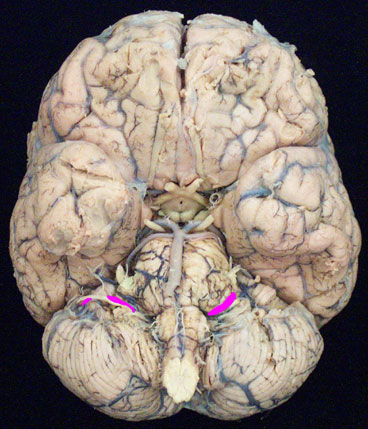

The facial nerve is primarily a motor nerve, but also carries special sensory (taste) fibers. CN VII emerges between the pons and medulla on the brain and exits the skull through the internal acoustic meatus, facial canal and finally the STYLOMASTOID FORAMEN. Branches of the facial nerve supply the MUSCLES OF FACIAL EXPRESSION, taste to the anterior two thirds of the tongue (chorda tympani), parasympathetic innervation to the submandibular and sublingual glands (chorda tympani), and the lacrimal glands and mucous glands of the soft palate, nose, and paranasal sinuses (greater petrosal nerve).